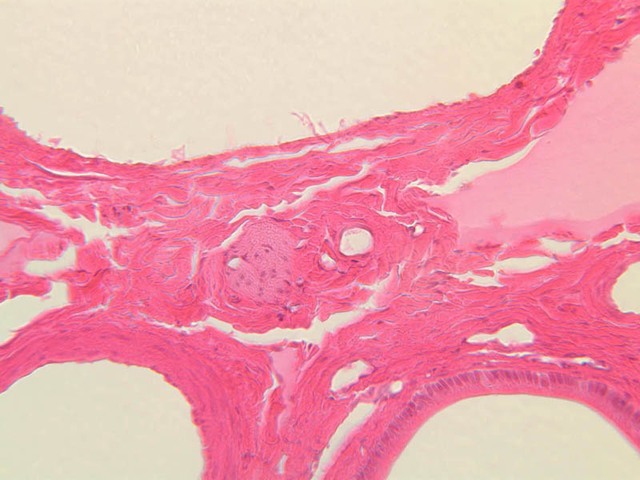

Using the 10X (B-29, B-30)and 40X (B-29) objectives, examine several portal triads, noting the variable number of profiles of hepatic artery, portal vein and bile duct that comprise the portal triad. Near the boundary between adjacent lobules, try to find some of the small elements of the bile duct system known as canals of Hering.

Using the high dry objective, study the lining of the central vein and hepatic sinusoids (B-29). In some places the hepatocytes are exposed directly to the sinusoidal lumen, but, as a rule, there is a basal lamina which supports a discontinuous mosaic of endothelial cells and specialized phagocytic cells known as Kupffer cells. Find examples of Kupffer cells and endothelial cell nuclei. Note that in some places you may see a narrow space (the space of Disse) between hepatocytes and the basement membrane underlying endothelial and Kupffer cells. Using the oil immersion (100X) objective, look very carefully along the boundaries between adjacent hepatocytes to see if you can find a bile canaliculus--the most delicate portion of the bile duct system--the walls of which are formed by the plasma membranes of adjacent hepatocytes.